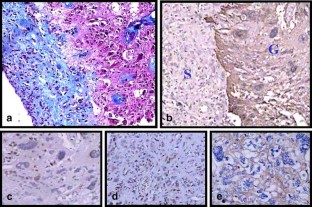

We report a rare case of childhood GCG in an 8-year-old boy surviving for more than 10 years since initial diagnosis. He has had two recurrences at the ages of 16 and 17 years, respectively, with histopathology at second recurrence showing evidence of gliosarcoma.

No such case of gliosarcoma following treatment for GCG has been reported in the literature. Hence, the origin of the gliosarcoma whether radiation induced or only a phenotypic change in the GBM remains conjectural.